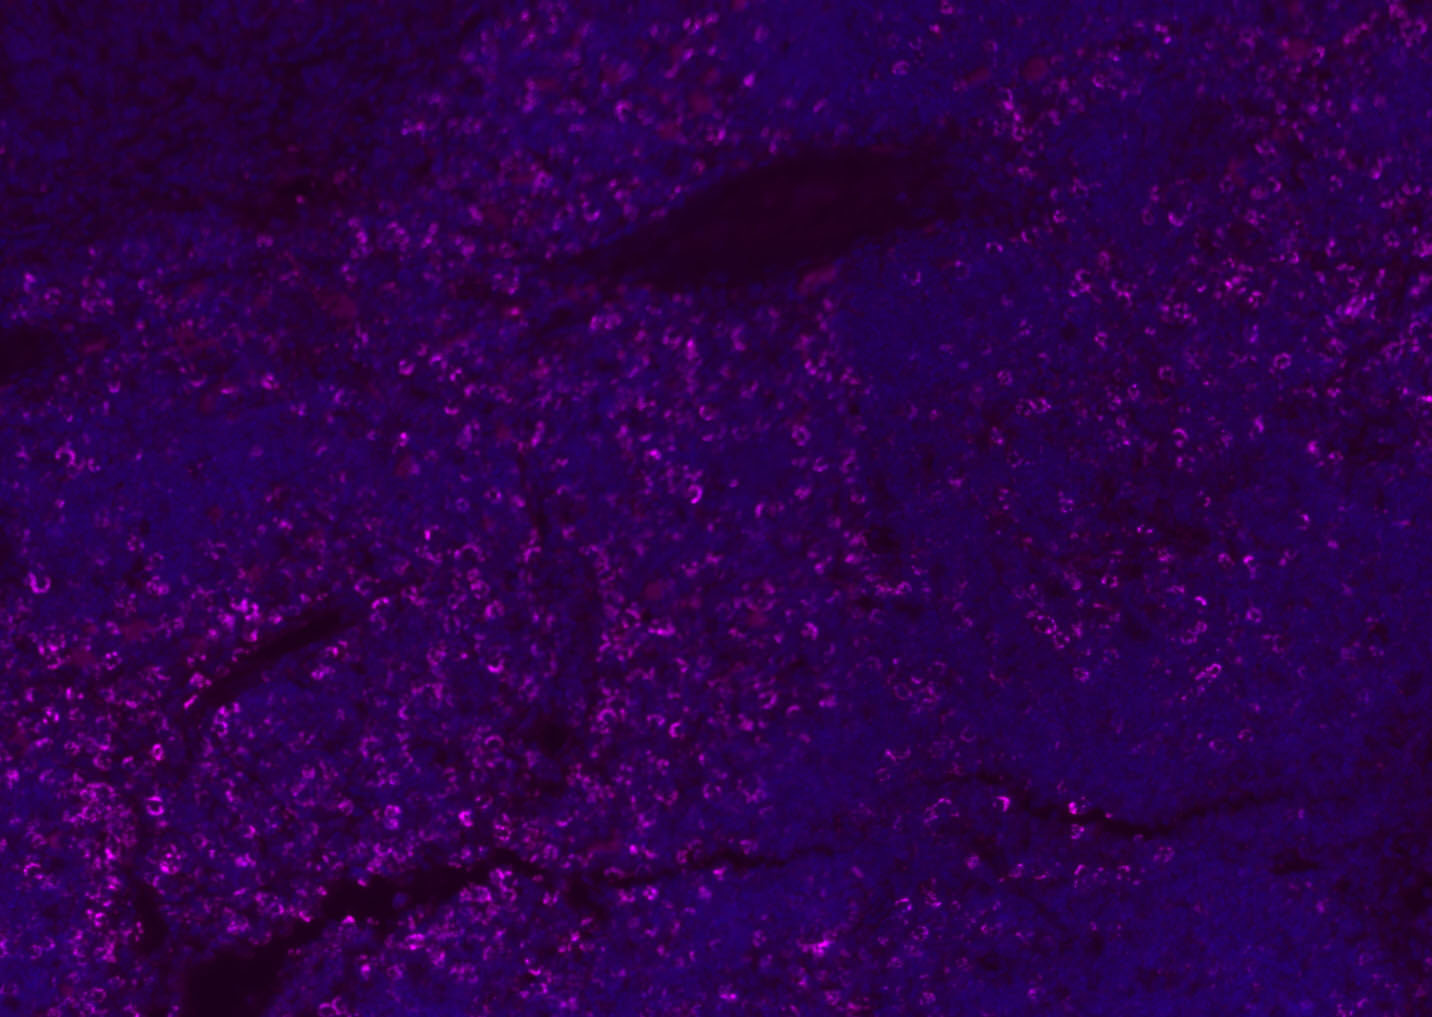

Tissue/cell: human lung carcinoma;4% Paraformaldehyde-fixed and paraffin-embedded;

Antigen retrieval: citrate buffer ( 0.01M, pH 6.0 ), Boiling bathing for 15min; Blocking buffer (normal goat serum,C-0005) at 37℃ for 20 min;

Incubation: Anti-CD8 Polyclonal Antibody, Unconjugated(bs-4914R) 1:200, overnight at 4°C; The secondary antibody was Goat Anti-Rabbit IgG, Cy3 conjugated(bs-0295G-Cy3)used at 1:200 dilution for 40 minutes at 37°C. DAPI(5ug/ml,blue,C-0033) was used to stain the cell nuclei